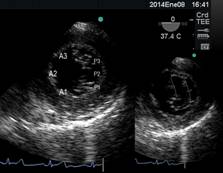

El análisis anatómico ecocardiográfico, se realiza con 2 D, y se basa en la adquisición de distintos planos que nos permitan observar el anillo, los velos y las comisuras en varias proyecciones.(Figura 7) Siguiendo un protocolo de 8 planos, que incluye 3 planos a nivel medio esofágico a 0° superior, donde se visualiza A1 y P1 además de la aorta y la orejuela, medio donde se ve A2 y P2, e inferior, casi llegando al seno coronario donde se encuentra A3 y P3. Luego entre 60° y 90°, a nivel del plano comisural, se ve P1, A2 y P3. Entre 80° y 100° en el plano de 2 cámaras, obtenemos la visión de A1, A2 y P3; con pequeños giros desde este lugar, podemos analizar todo el velo posterior y A2 y A3. Por último en esófago medio, el plano de 120° permite evaluar A2 y P2.(11)

Figura 7 Esquema de VM e imágenes de 4, 3 y 2 cámaras para comprender los distintos segmentos observados de las valvas mitrales, según el ángulo de visualización.

La imagen que nos permite ver integralmente ambas valvas y sus respectivos segmentos es la vista transgástrica a 0° (Figura 8) y la que nos facilita el estudio anatómico del aparato subvalvular y los músculos papilares es la transgástrica entre 80°-130°